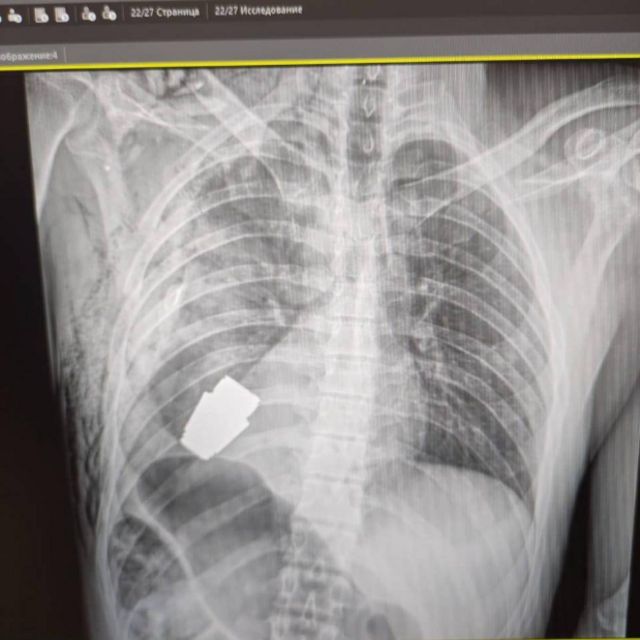

یوکرین میں فوجی ڈاکٹرز نے ایک غیر معمولی آپریشن کے دوران ایک فوجی کے جسم سے ایسا گرینیڈ نکال لیا جو پھٹا نہیں تھا۔

اس کامیاب آپریشن کے دوران زخمی فوجی کی چھاتی کے اندر تک گھس جانے والا چھوٹا ’وی او جی‘ گرینیڈ نکالا گیا۔ اس سرجری کے عمل کی اطلاع یوکرین کی نائب وزیر دفاع ہانا مالیار نے دی جنھوں نے اسے ’خوشی کا جھٹکا‘ قرار دیا۔

واضح رہے کہ روسی ساختہ وی او جی نامی گرینیڈ، جو یوکرین کے فوجی کے جسم میں موجود تھا، کا قطر تقریبا چار سینٹی میٹر اور وزن 275 گرام تھا۔